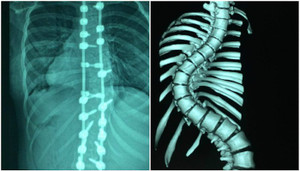

Bệnh nhân nữ 15 tuổi mắc hội chứng Marfan dẫn tới ngón tay, chân dài hơn người bình thường, cột sống bị vẹo 69°, cong như hình chữ S.

Một thiếu nữ 15 tuổi vừa cải thiện chiều cao thêm 7cm sau khi ca phẫu thuật nắn chỉnh cột sống bị vẹo đến hơn 100° thành công tốt đẹp.

Nhiều năm bị cong cột sống, cô bé được bác sĩ mổ nắn thẳng lưng giúp tăng thêm 7 cm và có thể tự tin mặc áo dài đi học.